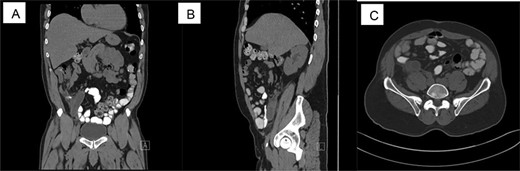

CT scan shows acute appendicitis. Dilated fluid-filled appendix measuring up to 2.4 cm in diameter × 8.3 cm in length with periappendiceal inflammation ((A) Coronal view, (B) sagittal view, (C) axillary view).

A 65-year-old male patient with a pertinent past medical history of hypertension, type 2 diabetes mellitus, alcohol and tobacco use presented with right-sided abdominal pain. The patient stated that the pain started 3 days prior, with a previous hospital visit the day before but the patient left against medical advice. The patient described the pain as sharp, intermittent, 8/10 and constant. He denied any fever, chills, nausea, vomiting, diarrhea, dysuria, any significant weight loss, changes in bowel habit or previous colonoscopy. His vital signs on presentation were temperature of 98.9°C, heart rate of 101 bpm, respiratory rate of 16 breaths/min, blood pressure of 117/68 mmHg and oxygen saturation rate of 95% on room air. On focused physical examination, the abdomen was tender to deep palpation in the right lower quadrant with a negative Rovsing’s sign, no rebound and no guarding, which correlates with a clinical diagnosis of acute appendicitis. Imaging showed a dilated fluid-filled appendix measuring up to 2.4 cm in diameter × 8.3 cm in length with periappendiceal inflammation as well as a trace left hydroureter and a non-obstructing right renal calculus. On admission, the patient had leukocytosis of 11.5 with a differential of 75.7% neutrophils and 14.5% lymphocytes. Patient was placed on intravenous antibiotics (Zosyn) and taken for laparoscopic appendectomy.

During surgery, the appendix was noted to be adhered to the abdominal wall and multiple adhesions to the surround mesentery at the base of the appendix. The appendix measured 10.5 cm in length × 1–2 cm in diameter when it was extracted and sent to pathology (Fig. 1). The serosa of the appendix was dull and hemorrhagic. There was a firm area measuring 2.5 cm at the base. On pathology, the cuts revealed a gray white homogeneous appearing tumor measuring 2.5 × 0.7 × 1.3 cm located at the proximal appendix with positive lymphovascular invasion (T3, NX, MX). Pathology results showed carcinoma of ex-goblet cell carcinoid, signet ring cell type (Fig. 2). Microscopic findings indicated the involvement of muscularis propria into subserosa of mesoappendix with the absence of tumor perforation. Immunohistochemical staining revealed positive staining for chromogranin and synaptophysin, supporting the diagnosis (Fig. 2).